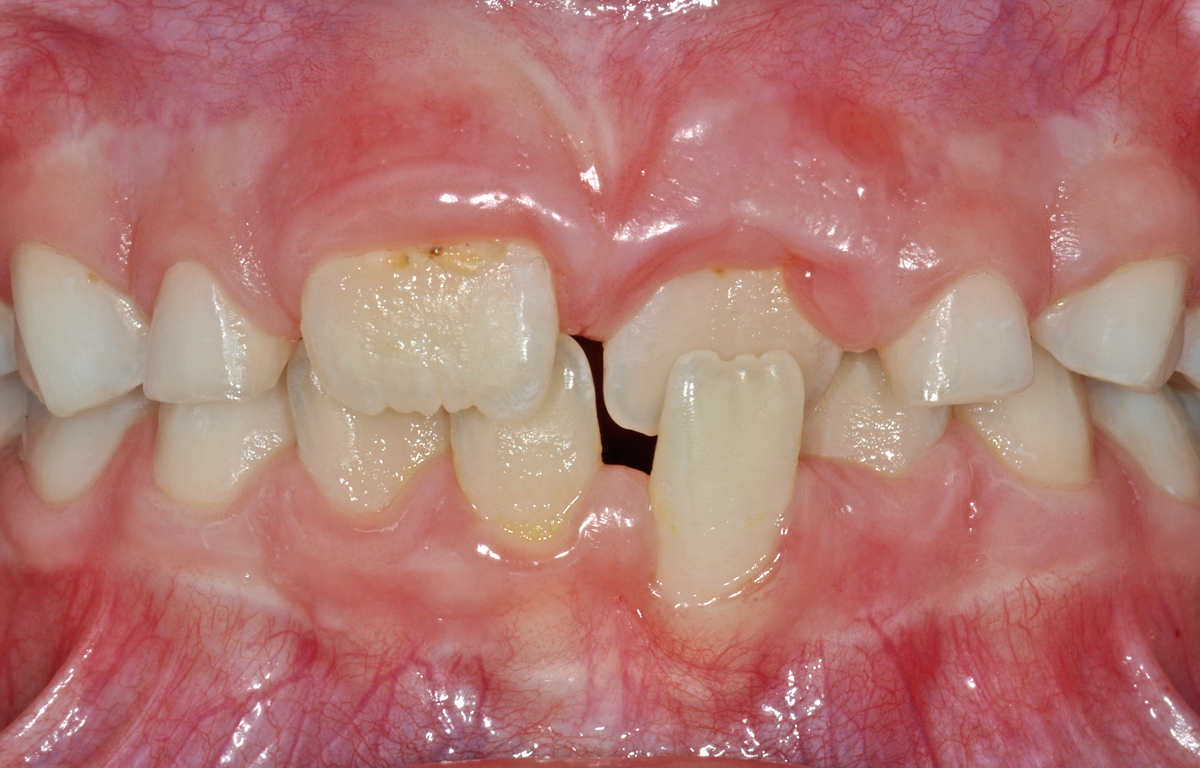

In diesem Beitrag zeige ich einen Fall eines zwischen 8 und 9 Jahre alten Patienten, der sogenannte Kreuzbiss-Situationen hat. Der Patient hat gleich zwei solche Kreuzbisse, nämlich einen bei den Frontzähnen (den Schneidezähnen) und einen auf der linken Seite im Seitenzahnbereich.

Kreuzbisse können einzelne Zähne betreffen oder ganze Zahngruppen oder Zahnbereiche.

Die dunklen Flecken auf seinen Zähnen sind so genannter «black stain» und kann mittels einer professionellen Zahnreinigung entfernt werden; siehe dazu auch den Beitrag mit den Verfärbungen.

Kreuzbiss im Frontzahnbereich

Auf dem ersten Bild ist eine Ansicht von vorne zu sehen. Die beiden mittleren Schneidezähne stehen vor den unteren Schneidezähnen und somit «richtig». Die seitlichen Schneidezähne sind nur knapp zu sehen und stehen deutlich hinter den mittleren oberen, aber auch hintern den unteren Schneidezähnen. Das nennt man einen Kreuzbiss in der Front.

Diese Abweichung ist dadurch bedingt, dass die seitlichen Schneidezähne zu weit auf der Gaumenseite (im zahnärztlichen Vokabular: palatinal) durchgebrochen sind. Nebst der ursprünglichen Lage der Zahnkeime beim Wachstum ist sicher auch die zu knappe Platzsituation (auf dem folgenden Bild gut zu erkennen) mit daran beteiligt.